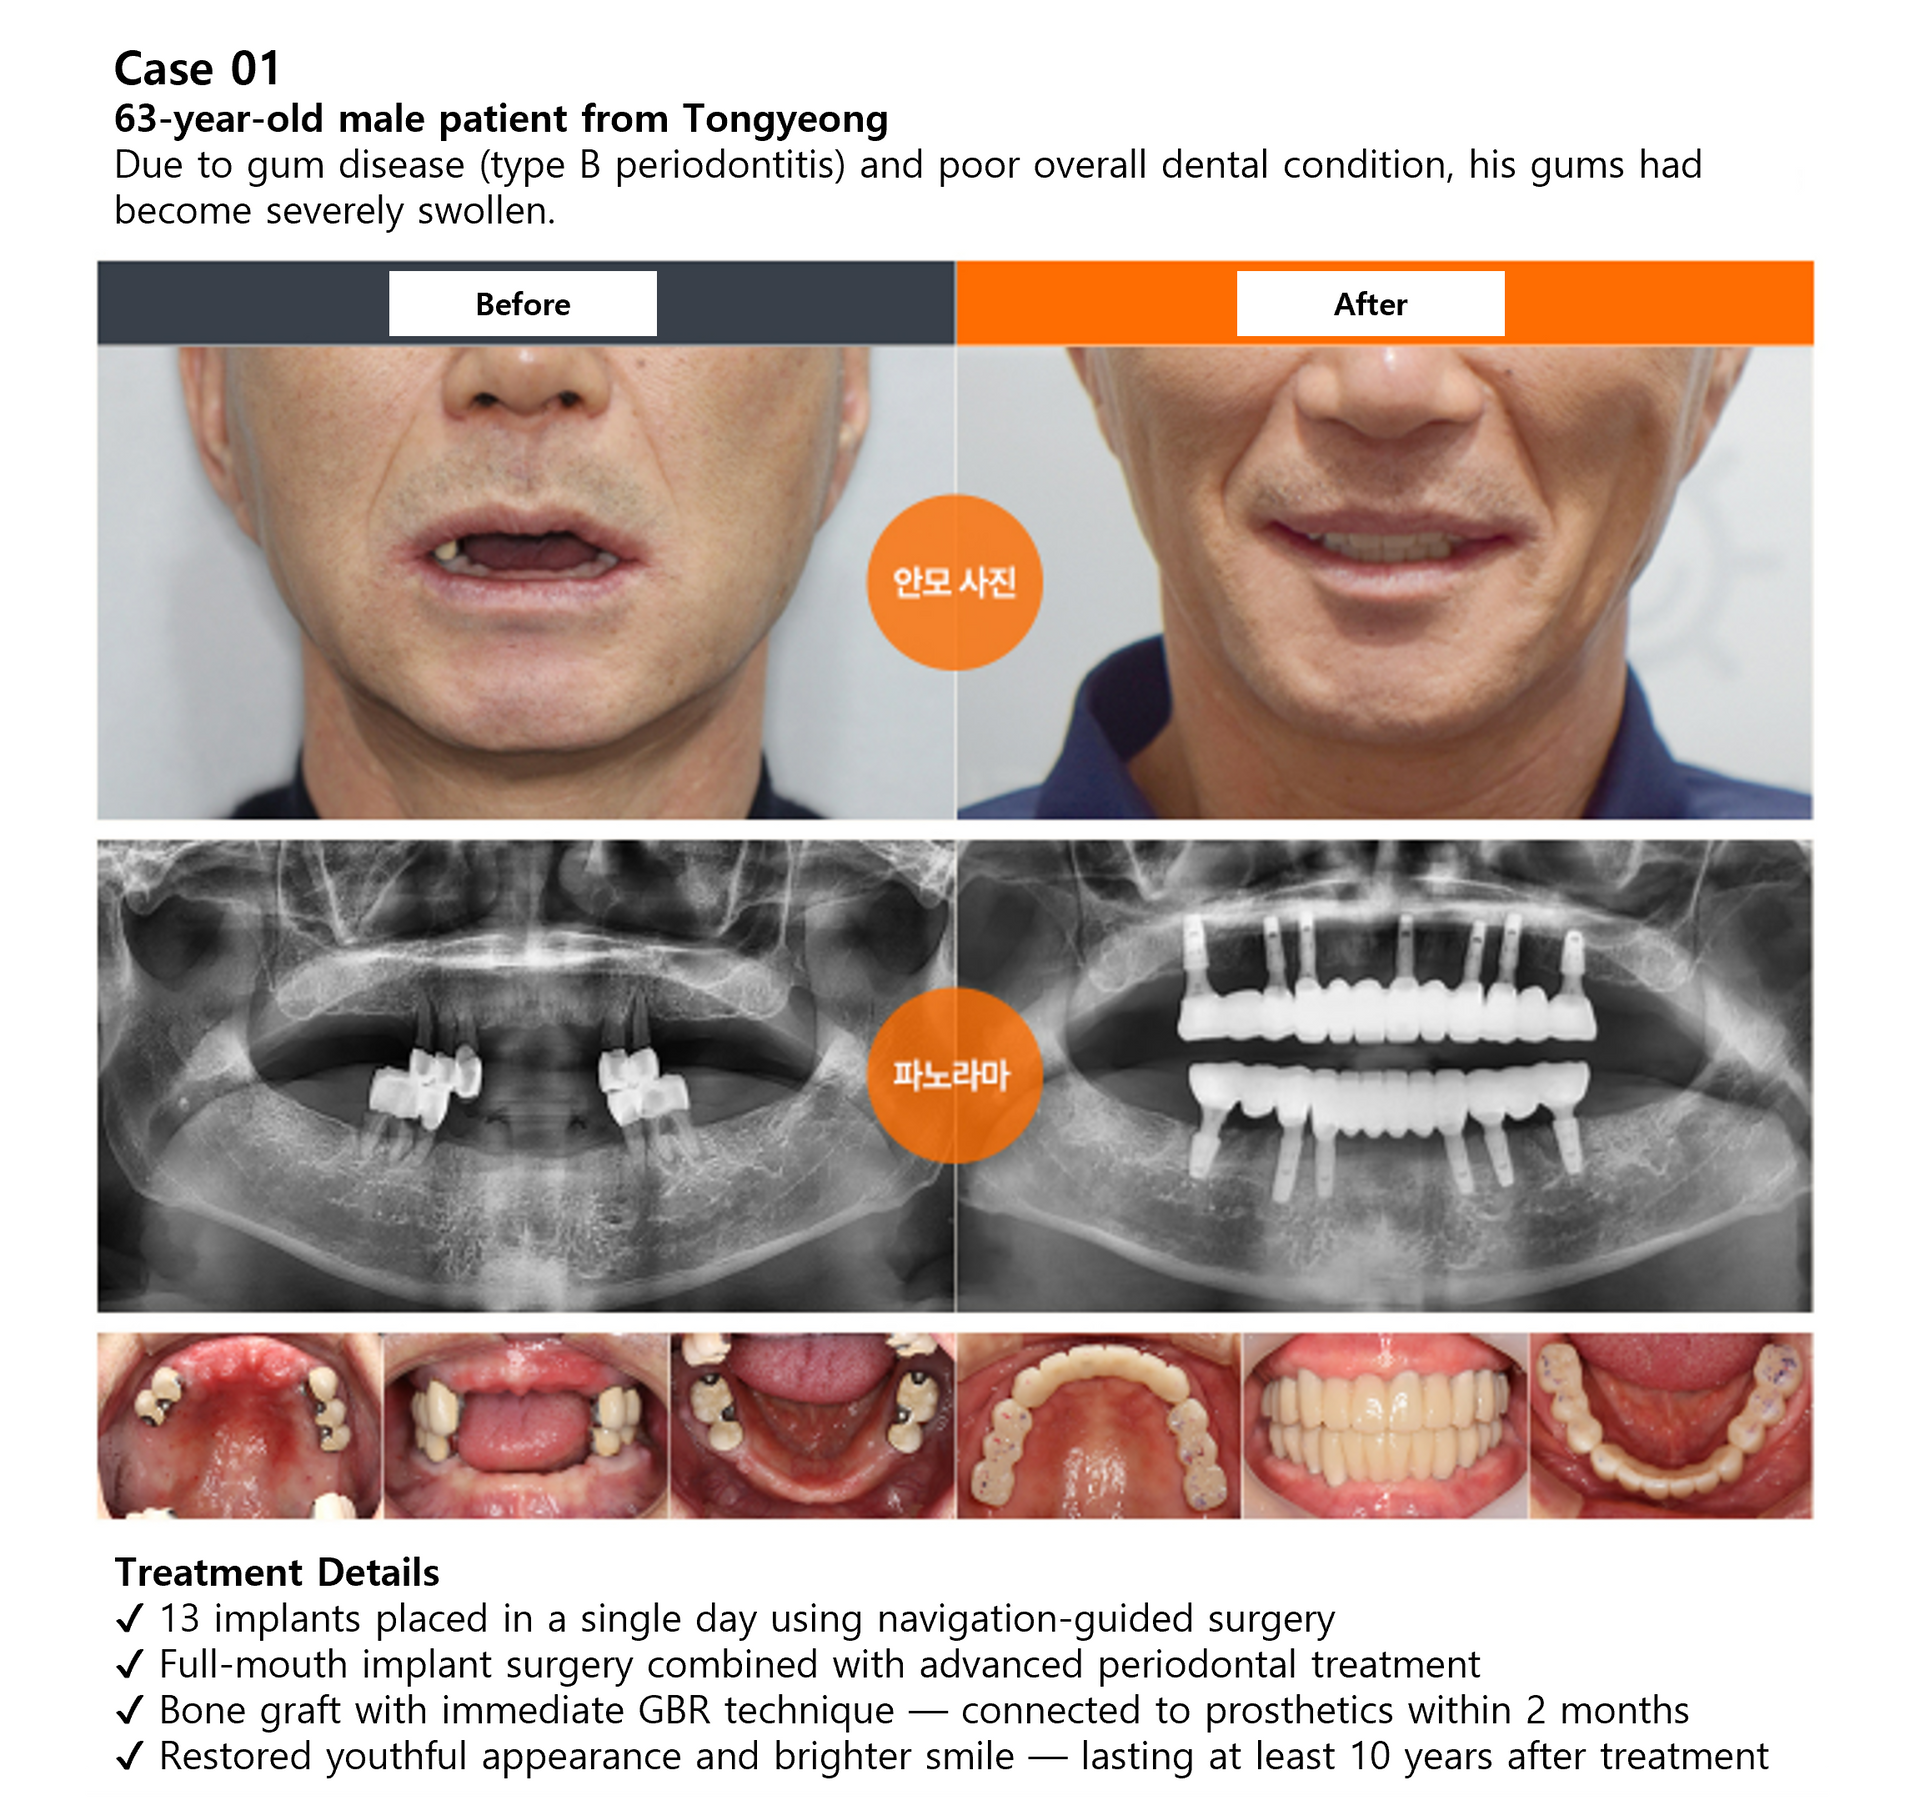

Case Review

Full Mouth Implant Before & After